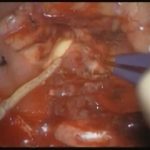

術中写真

摘出 前